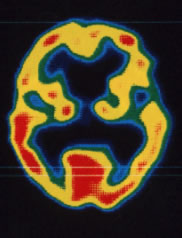

図:アルツハイマー型認知症

両側側頭頭頂葉の血流低下 (矢印)を認める。